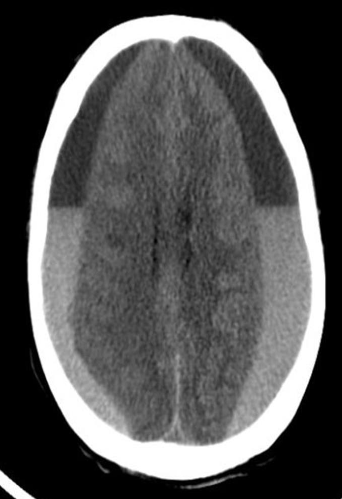

CT brain - Hydrocephalus